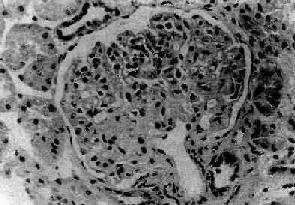

图12-21 局灶性节段性肾小球硬化

肾小球毛细血管丛的一段硬化,玻璃样变

病变为局灶性,往往从肾皮质深部近髓质部分的少数肾小球开始。早期仅少数肾小球受累,其他肾小球无明显病变或病变轻微。病变的肾小球毛细血管丛的部分毛细血管萎陷,系膜增宽、硬化、玻璃样变(图12-21)。系膜内和毛细血管内常有脂滴和玻璃样物质沉积。有时可见吞噬脂类的泡沫细胞聚积。电镜下可见硬化部分毛细血管基底膜皱缩,厚薄不均匀。其间可见电子致密物和脂滴沉积。上皮细胞足突消失。免疫荧光检查可见病变肾小球内有免疫球蛋白和补体沉积,主要为IgM和C3。